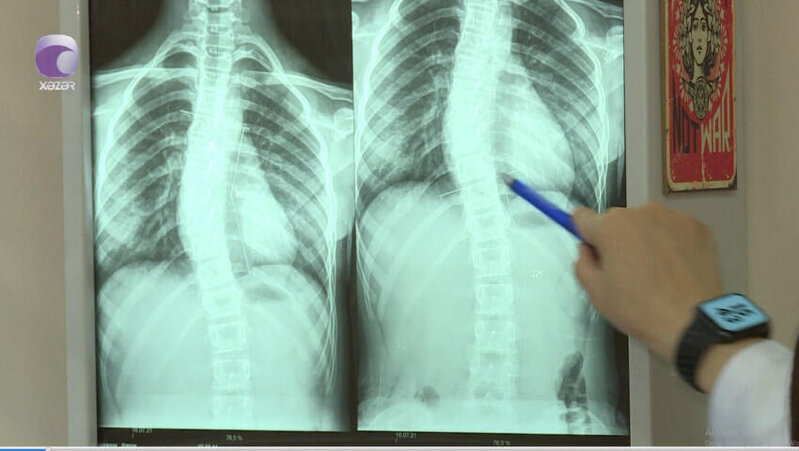

"Son zamanlar 8-12 yaş aralığındakı uşaqlarda bel və boyun ağrıları ilə bağlı şikayətlər nəzərəçarpacaq dərəcədə artıb.

Halbuki, illər öncə uşaqlarda belə problemlər olmurdu. Bunu fizioterapevt Səidə Kərimova "Xəzər xəbər"ə müsahibəsində deyib.

Milli.Az xəbər verir ki, həkim səbəb olaraq bildirdi ki, uşaqların çantaları kifayət qədər ağırdır. Çiyin ağrıları isə xüsusən ona görə yaranır ki, ağır çantaları daşıyarkən, kəmərləri uşağın yumşaq toxumasını sıxıb kəsir.

Həkim bildirdi ki, bu yaşda uşaqlar oturanda, xüsusilə də dərs oxuyarkən, qamətini dik tutmalıdır.